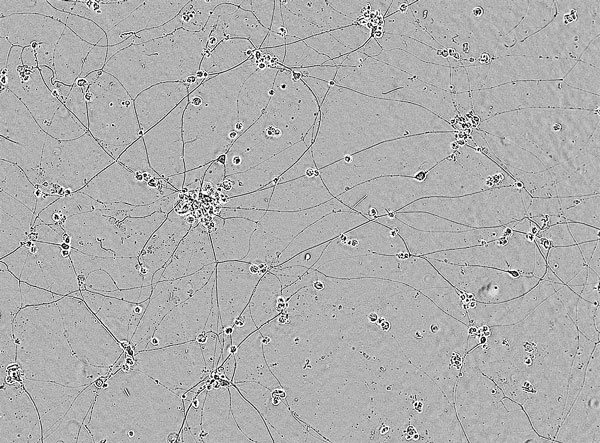

神経変性疾患モデル (神経傷害性老化アストロサイト × 神経細胞)

神経変性疾患モデルとなり得る神経傷害性アストロサイトによる神経細胞死誘導の系を用いて、化合物評価や探索、ネットワーク解析による疾患理解・新規標的探索、標的確認が可能です。